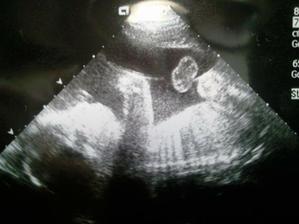

tak poradna proběhla v pořádku,přírustek váhy jen 0,5kg. UZ krásný, mimi spinkalo, nechtělo se pohnout, ale nakonec se protáhlo, cukalo nožičkama, ukazovalo nám jen prdelku, páteř, pak i na chvilku obličej...s krásnou velkou pusinkou asi po tatínkovi a velkýma očima po mamince. Máme dvě ručičky,nožičky,prdelku jak česnek,nosánek...srdíčko krásně tlouklo...